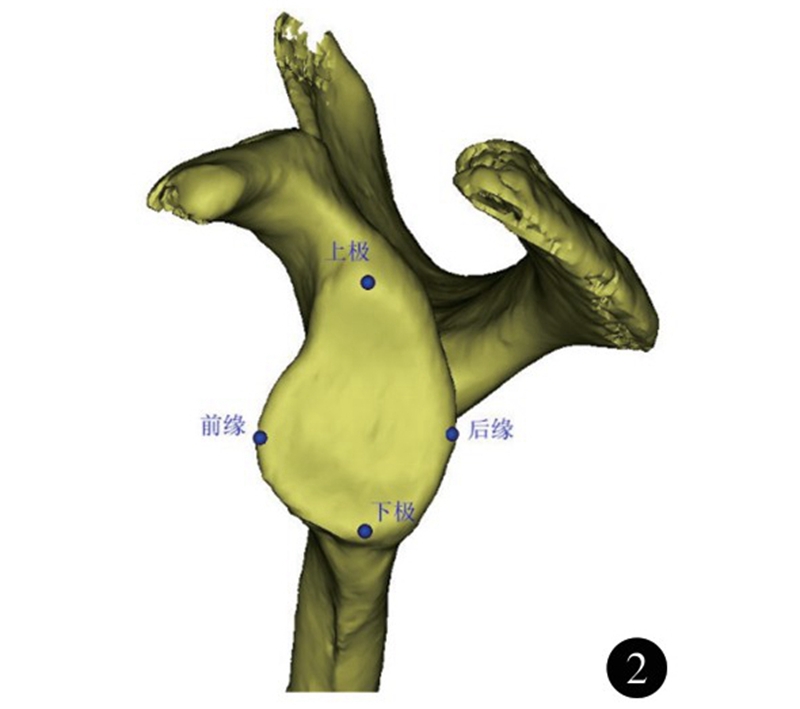

肩胛骨位于胸廓上方两侧偏后,紧贴胸后壁,与其构成类似关节的结构,称之为肩胛胸壁关节。肩关节活动时,肩胛骨沿胸壁活动,配合盂肱关节,完成肩关节上举,是肩关节的重要组成,并通过盂肱关节和肩锁关节将上肢连接于躯干上。肩胛盂作为盂肱关节的组成部分,深度较浅,形态不规则,近似梨形;下半部分较上半部分大,比例约为1∶0.8±0.1。众多研究测量了肩胛盂表面解剖学参数,其中肩胛盂上下径为肩胛盂最高点至最低的距离(图2);其均值男女分别为33.6~37.5mm和29.4~33.8mm。肩胛盂前后径为位于与肩胛盂上下轴垂直平面的肩胛盂前后的最大距离;其均值分别为24.9~28.6mm和21.3~23.7mm。肩胛盂上下径、前后径存在显著的性别差异,男性肩胛盂较女性大10%左右。肩胛盂形态在性别上也有不同,男性肩胛盂下部较圆,而女性为椭圆。Andrea等依据肩胛盂前缘切迹的形态将肩胛盂的形状分为4型(图3):0型(无切迹)、Ⅰ型(弧线型)、Ⅱ型(切迹型)、Ⅲ型(圆齿型)。男女均以Ⅰ型(弧线型)所占比例最高。肩胛盂前缘切迹在女性中出现的比例为80.4%;而男性中这一比例为57.6%。36.7%的女性切迹出现在顶部;而男性只有28.9%,两者差异有统计学意义。

图2 肩胛盂上下径、前后径示意图